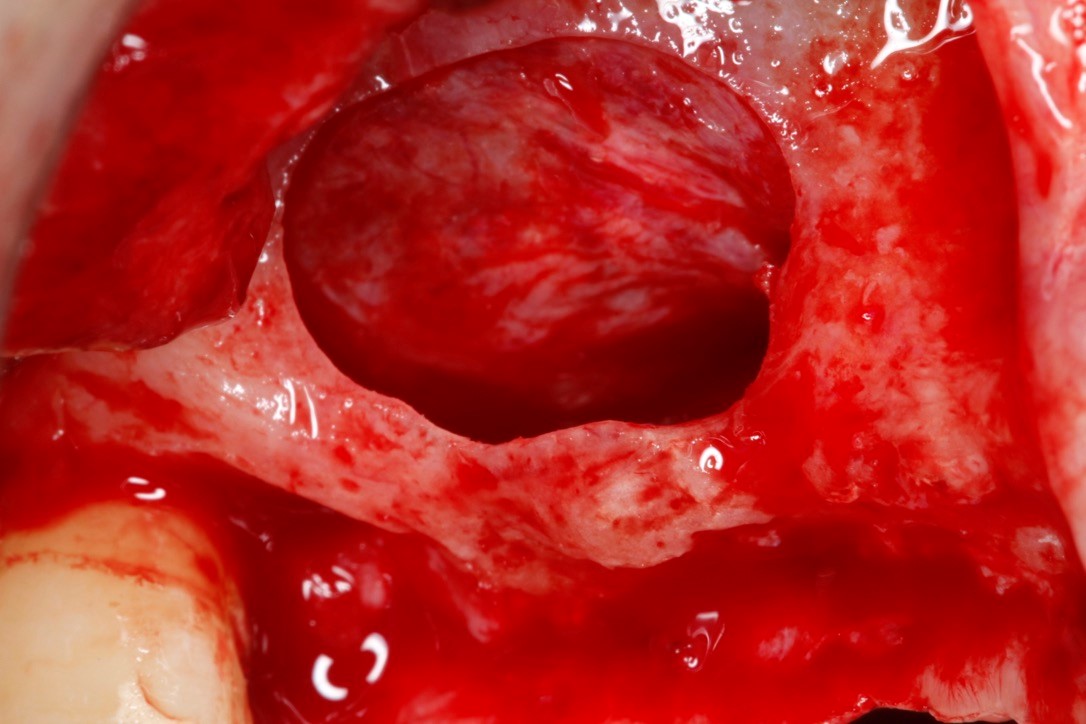

- Синус-лифтинг

- Реконструктивные вмешательства

• СДТ (вестибулярно)

• СДТ (по гребню)

• Метод валика

• Субэпителиальный СТТ

• СТТ – конвертный метод

• СТТ – метод VISTA